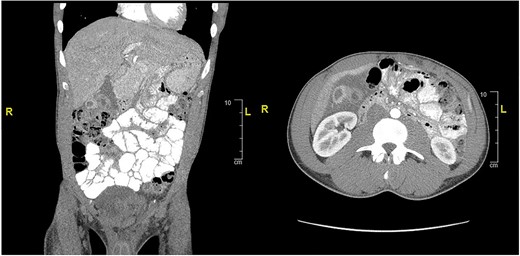

CT of abdomen and pelvis showing an inflamed gallbladder with fistulous communication within the hepatic flexure of the colon. Large descending colon enterolith (4.5 × 4.3 × 8.0 cm). Apparent pneumobilia.

CT of abdomen and pelvis showing peripherally hyperdense septated collection within the porta hepatis with surrounding fluid signal attenuation likely representing an abscess seen around the gallbladder.